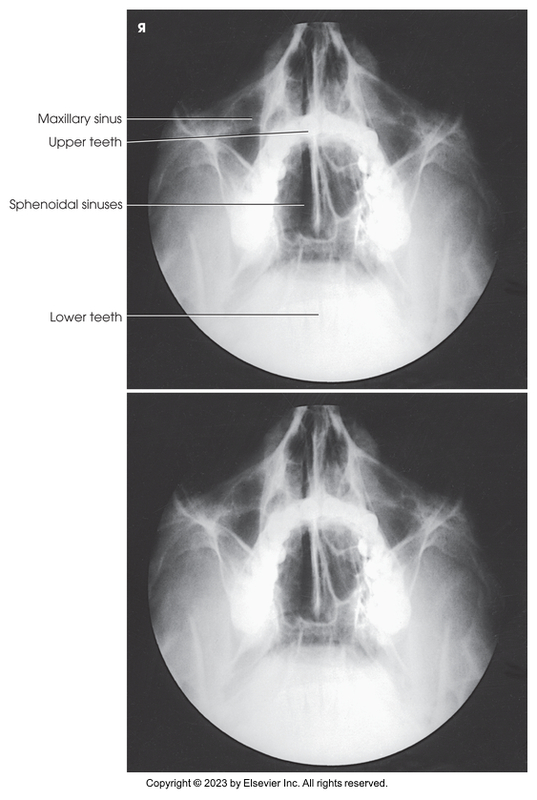

Parietoacanthial of the Maxillary and sphenoidal sinuses - open-mouth waters method

Parietoacanthial of the maxillary and sphenoidal sinuses (Open-mouth waters method)